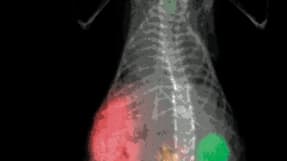

Traditional research on disease mechanisms in animal models mainly has relied either on the detection of morphological changes of the diseased tissues obtained through anatomical...